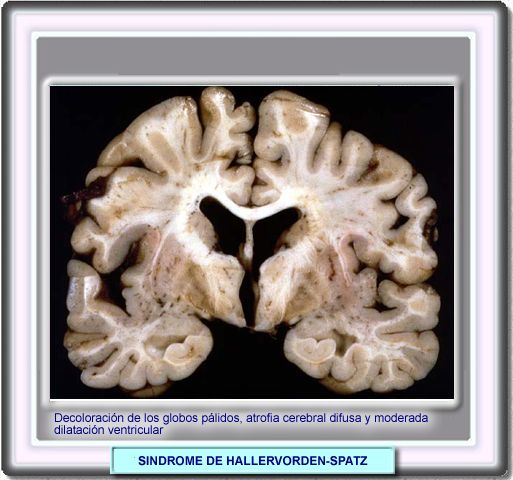

SINDROME DE HALLERVORDEN-SPATZ [ICD-10: E78.3]